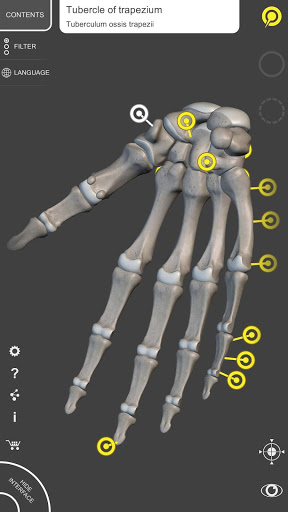

Mỗi xương của bộ xương người đã được tái tạo ở dạng 3D, bạn có thể xoay và phóng to từng mô hình và quan sát chi tiết từ mọi góc độ.

Bằng cách chọn mô hình hoặc ghim, bạn sẽ được hiển thị các thuật ngữ liên quan đến bất kỳ bộ phận giải phẫu cụ thể nào, bạn có thể chọn từ 12 ngôn ngữ và hiển thị các thuật ngữ bằng hai ngôn ngữ cùng lúc.

• Xoay và Phóng to mọi mô hình trong không gian 3D

• Ghim tương tác cho phép trực quan hóa thuật ngữ liên quan đến mọi chi tiết giải phẫu